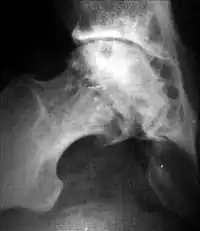

Диспластический коксартроз

Диспластический коксартроз развивается на фоне дисплазии тазобедренного сустава чаще в возрасте 25–55 лет, на фоне гормональной перестройки организма при беременности и в послеродовом периоде, а также на фоне снижения двигательной активности и ухудшения функционального состояния мышц тазобедренного сустава. Обычно начало заболевания связывают с прекращением занятий спортом, снижением активного образа жизни, травмой сустава или родами.

Начало заболевания острое, течение – быстро прогрессирующее.

Клинически диспластический коксартроз проявляется «неудобством», неприятными ощущениями в области тазобедренного или коленного сустава, ограничением отведения и ротации бедра. В начальной стадии рентгенологически определяются краевые разрастания в области верхне-наружного края вертлужной впадины, уплотнение костной пластинки в области крыши данной впадины. В поздних стадиях определяется кистовидная перестройка головки бедренной кости и ацетабулярной области, которую необходимо отличать от зон перестройки при асептическом некрозе головки бедренной кости. Исход заболевания – анкилозирование сустава с формированием порочной установки бедра в положении сгибания, приведения и наружной ротации. В отличие от иных форм коксартроза (артроза после травмы сустава и асептического некроза головки бедренной кости), анкилоз сустава встречается достаточно редко. Показанием к хирургическому лечению (эндопротезированию тазобедренного сустава) является болевой синдром и порочная установка бедра[25].